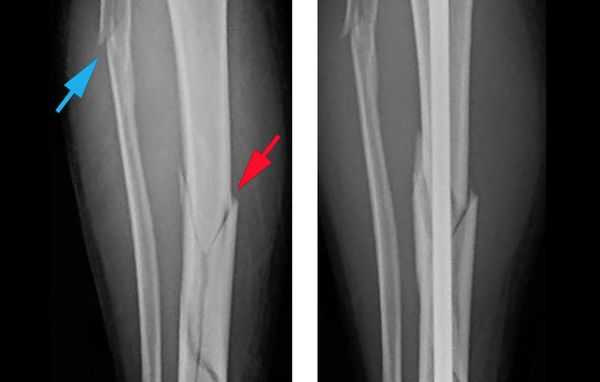

Объективно подтвердить диагноз позволяет рентгенологическое исследование голени в двух стандартных проекциях: прямой и боковой [8] . Чтобы избежать ошибок, рентген следует выполнять строго по стандартным укладкам.

![Рентгеновский снимок при переломе голени]()

Шок, вынужденное неестественное положение ноги из-за боли, наличие шин и фиксаторов затрудняют диагностику перелома. Если металлические шины или фиксаторы мешают сделать качественный снимок, то их придётся снять. Когда положение ноги не позволяет сделать снимок, её вправляют под местной анестезией.

В некоторых случаях, если требуется детальная диагностика нескольких сегментов голени или пациент находится в тяжёлом состоянии, показана компьютерная томография с 3d-реконструкцией кости. Исследование можно проводить и при вынужденном положении конечности, но такой томограф есть не во всех клиниках. Поэтому в некоторых случаях, если информации недостаточно, делаются уточняющие прицельные рентгеновские снимки отдельных сегментов кости.

![Компьютерная томография голени]()